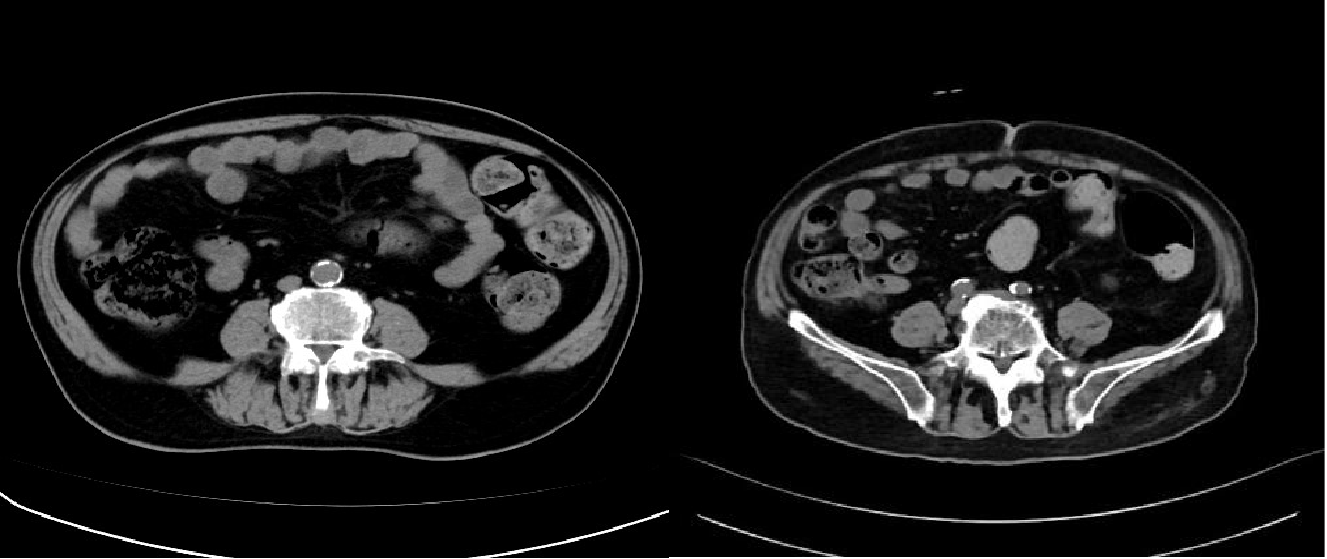

2023年9月16日,患者因气喘,复查胸腹部增强CT(图5):符合右肺上叶病变粒子植入表现、符合右肺下叶及左肺上叶纤维灶、结节灶,邻近支气管扩张、COPD,左侧肾上腺结节。痰培养:铜绿假单胞菌。后多次因肺炎给予抗炎治疗。

2024年2月,患者因言语错乱来院完善颅脑增强MR(图6):双侧放射冠区多发缺血灶;左侧小脑幕上异常信号灶,考虑脑膜瘤。患者因间断背部疼痛,院外口服"羟考酮20mg q12h、普瑞巴林75mg bid"治疗。

2024年4月,查胸部强化CT(图7):符合右肺上叶病变粒子植入表现,较前略增大;符合右肺下叶及左肺上叶纤维灶、结节灶,邻近支气管扩张;COPD、右侧胸腔积液、左侧肾上腺结节较前大致相仿。患者家属拒绝再次活检及静脉化疗。